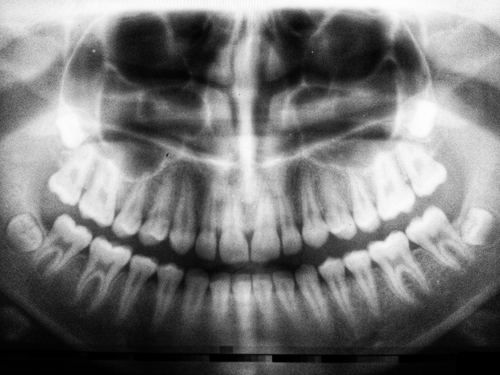

I recently had a sinus membrane lift with an underlying bone graft in my upper jaw to allow placement of a dental implant. Will I have any short- or long-term restrictions on diving?

Surgeons have not developed uniform recommendations related to oral surgery and scuba diving. Generally, the more complicated the surgery, the longer the wait before diving. Surgical complications, any underlying medical conditions, tobacco use and alcohol consumption can add to this waiting period.

During post-surgical osseointegration (fusion of the implant into the bone), it is necessary to avoid any activity that could apply pressure to the skin over the implant and cover screw or the healing abutment. Diving’s resultant pressure, no matter how slight, could damage the site if occurring too soon after surgery. If the regulator’s bite tabs are over the implant site, for example, transmitted biting forces can result in implant failure.

Diving should also be suspended for as long as it takes to avoid other complications associated with oral surgery: re-vascularisation (resumption of blood flow), stabilisation of the implant, oral and sinus cavity pressure changes, ability of the patient to hold a regulator in the mouth and use of medications for pain or infection. Bone grafting procedures and sinus surgery are more complex and will require a longer waiting period. The larger the graft site, the longer the wait. Some doctors recommend avoiding any activity that causes micro-movement for at least six months. It can take up to one year for complete bone healing at an implant site. Diving sooner than one year may not cause a problem, but your surgeon should determine the appropriate waiting period, and you should follow his or her advice.